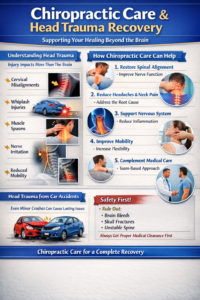

3. Neck Injuries and Stingers

Contact sports and poor posture can lead to neck injuries, stiffness, or nerve symptoms into the arm. Gonstead cervical adjustments are known for their specificity and safety when addressing these issues.

How Gonstead Adjustments Help Athletes Heal Faster

Healing is not just about reducing pain—it’s about restoring normal function. Gonstead adjustments help by:

- Reducing nerve interference

- Improving joint mobility

- Enhancing muscle coordination

- Supporting proper biomechanics

- Allowing the body to heal naturally